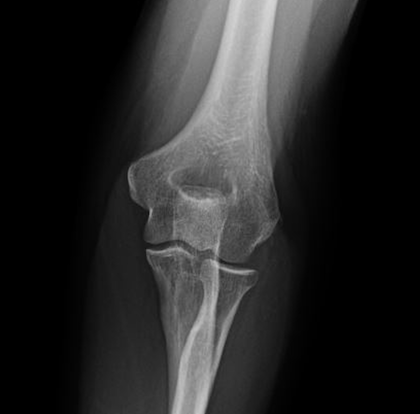

- This one-hour postgraduate lecture provides a focused, clinically practical approach to the evaluation of elbow pain and dysfunction. Emphasis is placed on functional anatomy, common injury mechanisms, orthopedic examination techniques, and the appropriate use of imaging in both acute and chronic elbow conditions. Participants will learn to integrate physical examination findings with imaging and case-based reasoning to improve diagnostic accuracy, identify red flags, and guide conservative care versus referral decisions.

- Imaging considerations for acute and chronic elbow pain

- Key differential diagnoses: epicondylitis, ligament injury, bursitis, nerve entrapment, and occult fracture

- Correlate examination findings with imaging to refine differential diagnoses.